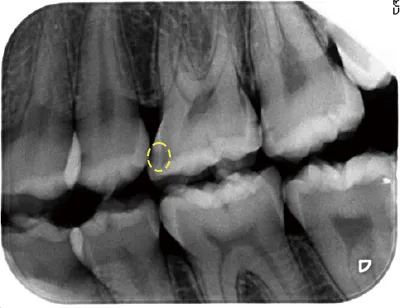

初期う蝕から2週間後にエナメル質の結晶が戻った

写真2 2週間後

このような状態をエナメル質初期う蝕(Ce)と呼び、この段階では、歯を削らずに治す「非修復治療」が適応となります。写真2の歯は2週間で溶け出したエナメル質の結晶が、また歯に戻って来ました(再石灰化)。